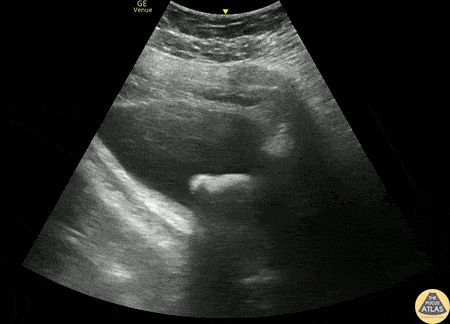

Renal/GU - Bladder Stone

70s M with past medical history of BPH and multiple recent UTIs presented as a referral to the ED after an outpatient CT KUB showed a large bladder stone. POCUS was performed and demonstrates a >3cm bladder stone present which obstructs urinary outflow. The patient was admitted and taken for surgery the next day. Phillip Breslow MD, Resident, Denver Health Residency in Emergency Medicine Mike Heffler MD, Ultrasound Fellow, Denver Health Ultrasound Fellowship